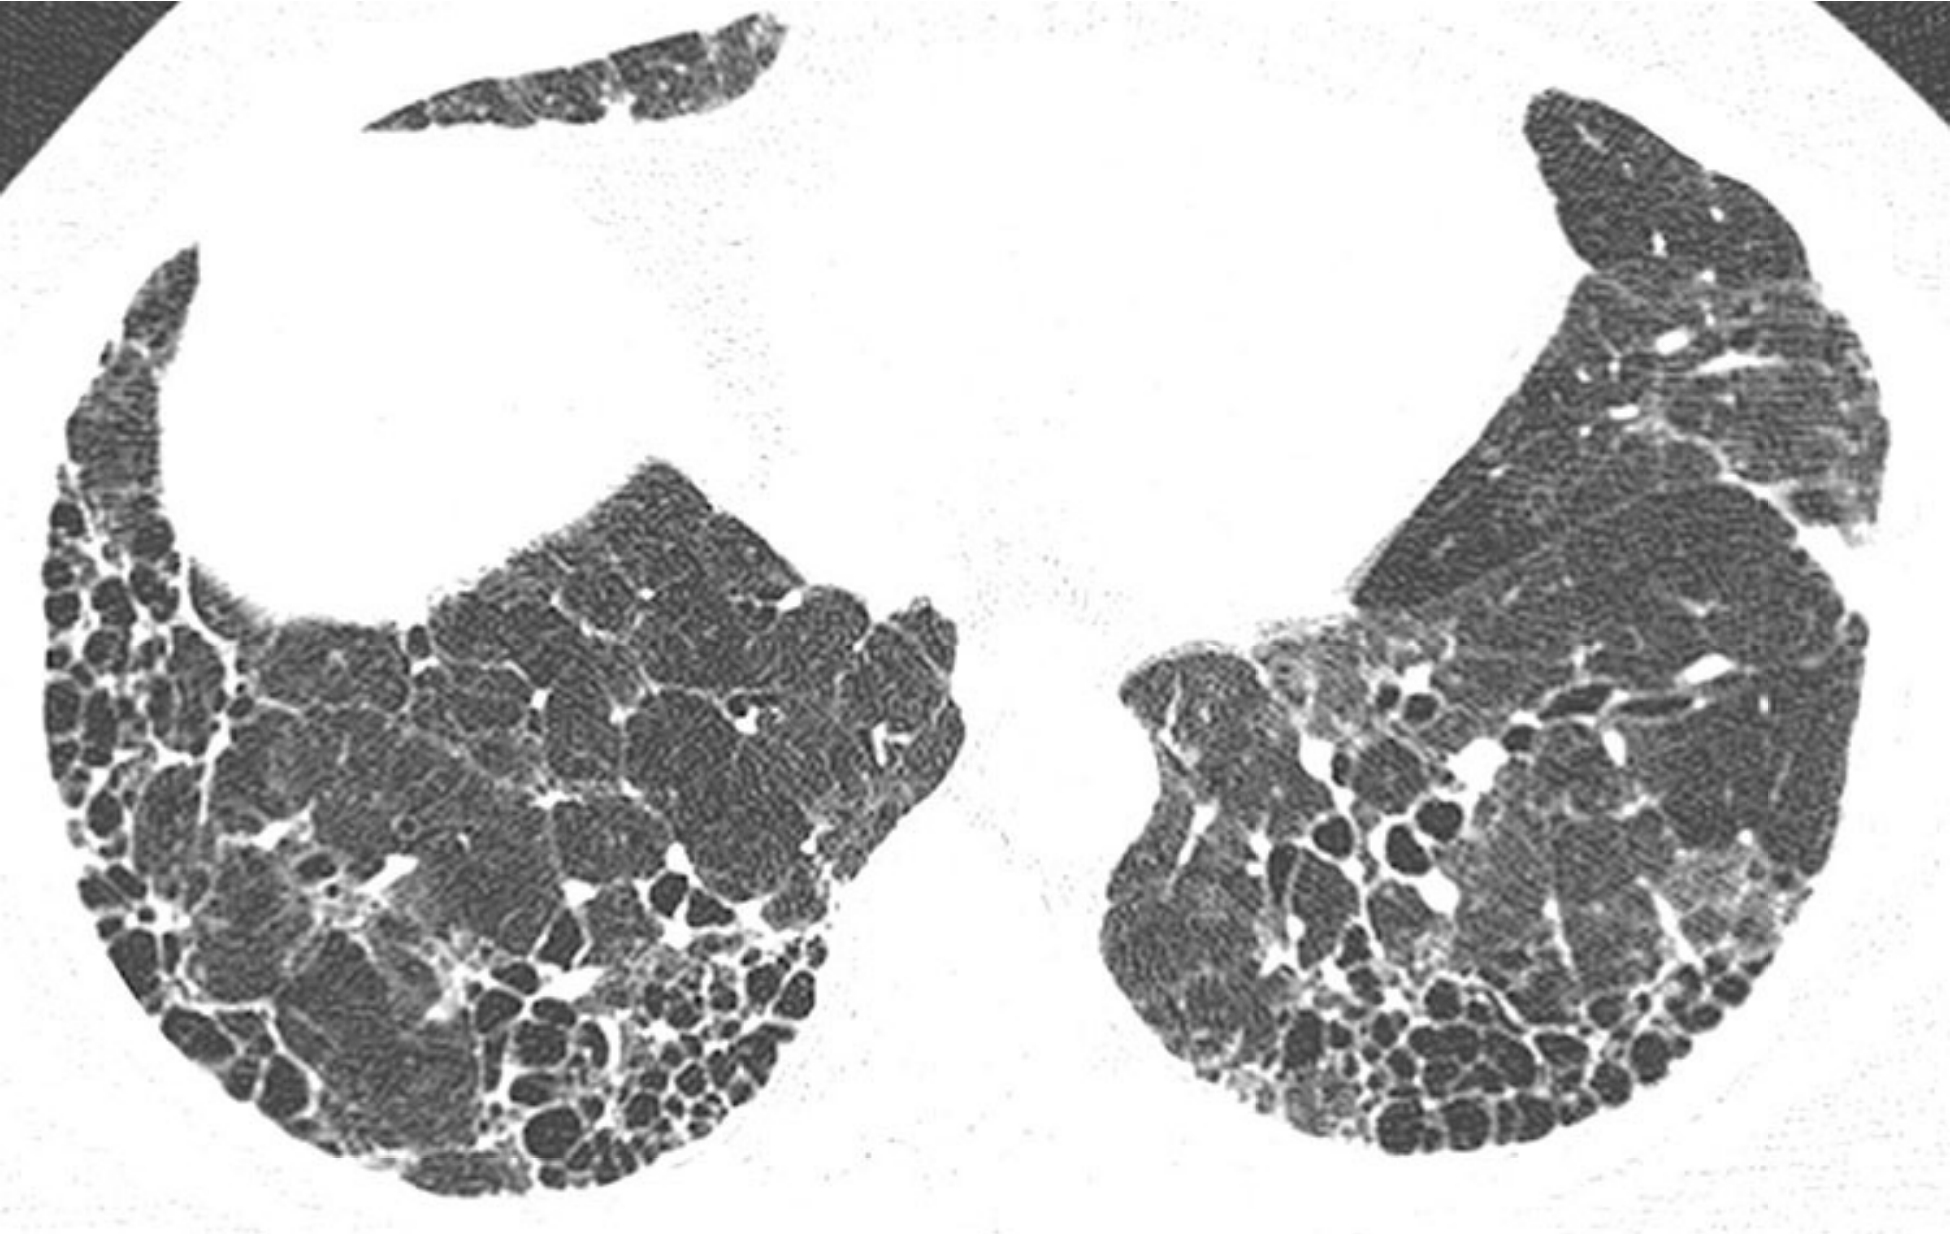

1d6b3eec372d7c316be21a0d6fbe74cc.jpg

家族性肺纤维化。

同一家族的2例家族性肺纤维化(A和B);活检证实,其组织学类型为普通型间质性肺炎(UIP)。

A. 1例患者表现为肺基底部分布为主的斑片状GGO和轻度牵拉性支气管扩张,B.另一患者表现为肺上叶和中央区分布为主的网状影、牵拉性支气管扩张和肺囊肿。家族性肺纤维化患者的HRCT表现通常不典型。